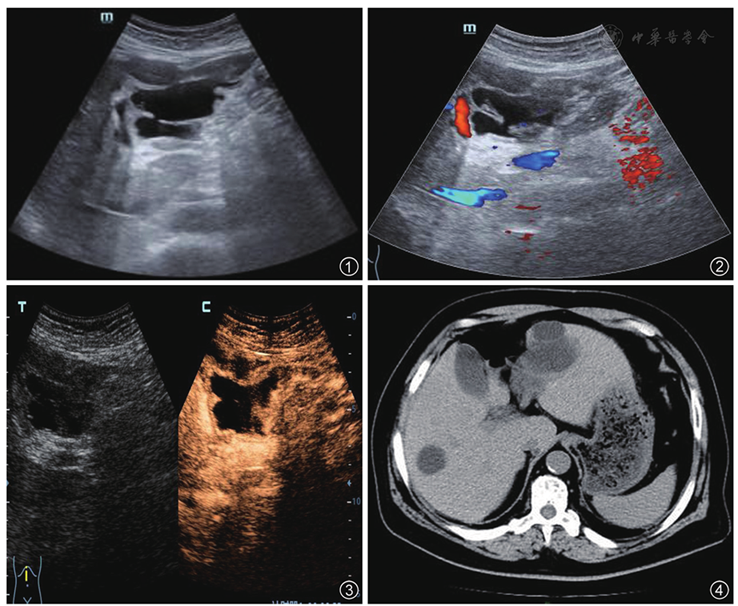

肝囊肿破裂超声造影表现一例

图4 CT示肝内可见多发类圆形、不规则低密度影,其内可见分隔